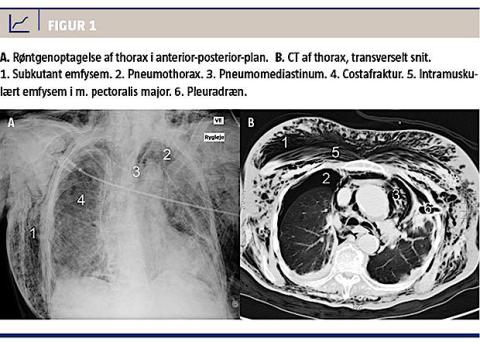

En røntgenundersøgelse af thorax viste massivt subkutant emfysem, venstresidig pneumothorax, højresidig costafraktur og mulig højresidig pneumothorax (Figur 1). Det udtalte emfysem vanskeliggjorde tolkning af røntgenbilledet. Der blev anlagt venstresidigt pleuradræn. Der blev udført en CT af thorax og abdomen, hvor man fandt bilateral hydropneumothorax, subkutant emfysem, pneumomediastinum samt fraktur af højresidige costae VI, VII og VIII. Pleuradrænet penetrerede accidentelt venstre lunges overlap. Der blev anlagt højresidigt pleuradræn, og placering af venstresidigt dræn blev korrigeret. Patienten blev indlagt på en intensivafdeling. Den bilaterale pneumothorax og larynxødemet regredierede. Hun blev ekstuberet efter to dage og efter tre dage overflyttet til stamafdelingen, hvor drænene blev seponeret. I efterforløbet udvikledes der en højresidig pleural ansamling, der blev behandlet med dræn og efterfølgende pleuracentese, da ansamlingen recidiverede. Patienten blev udskrevet til en rehabiliteringsplads.